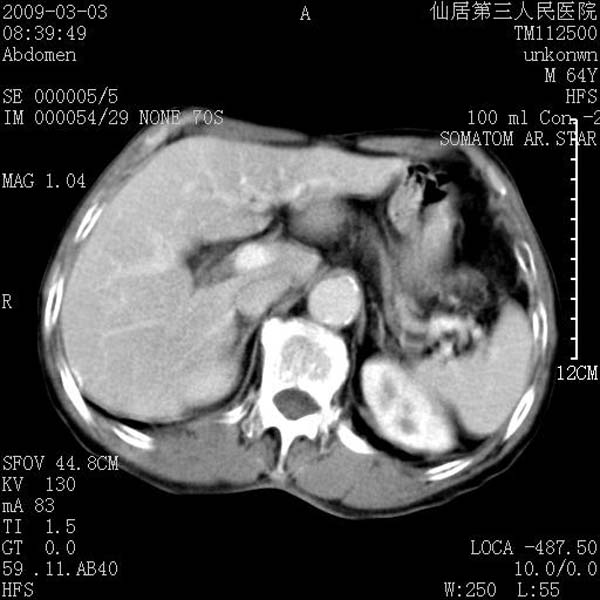

标题: CT18469:男性,64y,体检B超示肝脏低回声肿块,有胃溃疡手术 [打印本页]

标题: CT18469:男性,64y,体检B超示肝脏低回声肿块,有胃溃疡手术

患者,男性,64y,体检b超示肝脏低回声肿块,有胃溃疡手术史。

考虑----胃肠道间质瘤可能性大

从平扫及增强的特点来看,支持肝脏腺瘤并出血。

考虑胃间质瘤可能性大。

胃肠道间质瘤!

ct值呢?感觉没强化,象囊性。

考虑肝囊肿并出血可能性大.

考虑高密度囊肿可能性大